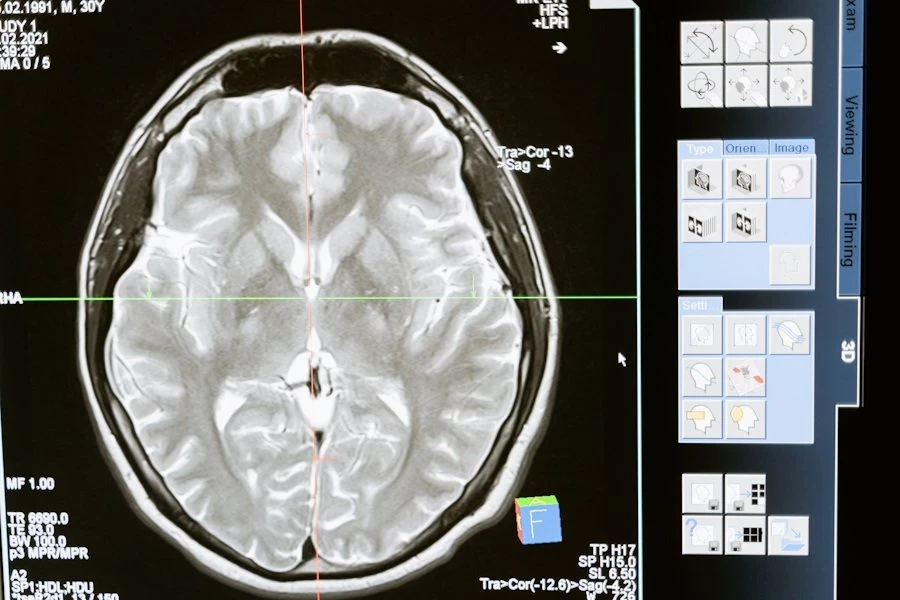

Для анализа использовались данные визуализации мозга 10 949 человек в возрасте от 45 до 82 лет и образцы крови почти 5 000 участников. Учёные также подтвердили причинно-следственную связь между уровнем BCAN и ускоренным старением мозга с помощью генетического метода Менделевской рандомизации.